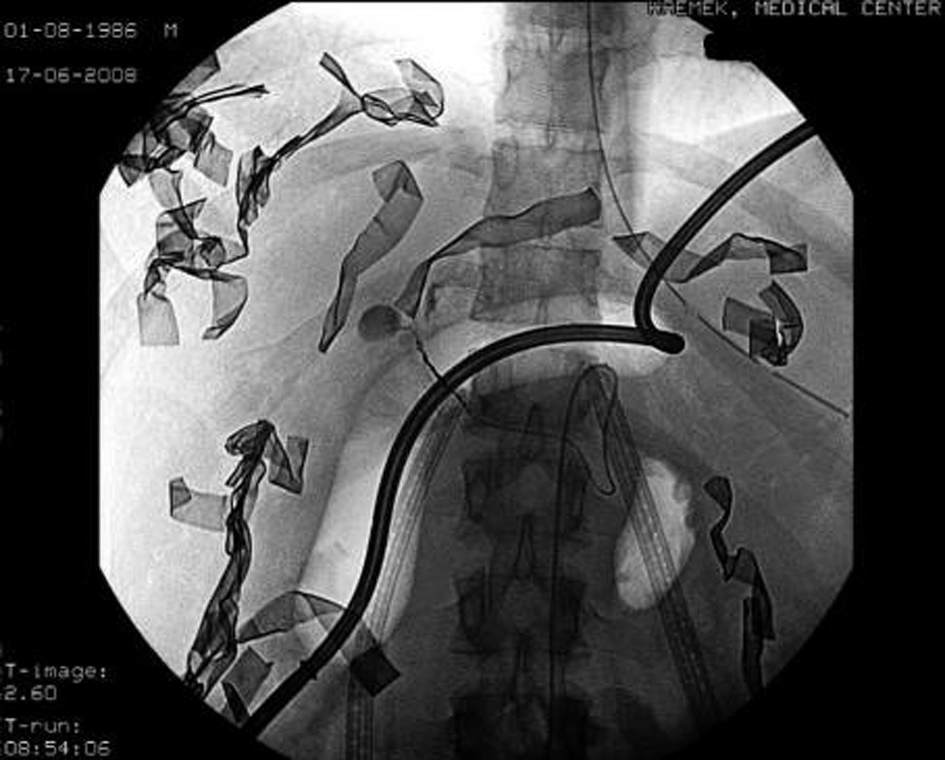

Despite liver mobilization with subsequent packing and an attempted Pringle maneuver, a significant amount of bleeding was observed through the wounds. A Sengstaken-Blakemore tube was placed through the wound to the depth of the liver. The esophageal balloon was inflated with air to tamponade the bullet tract (Fig. 1). This maneuver significantly decreased the bleeding but did not completely stop it. The gauze packs were left in place, the diaphragm laceration was sutured and temporary abdominal closure with vacuum pack system was performed. A right chest tube was inserted with an initial output of 250 mL of blood. Throughout the surgery the patient was transfused with 6 L of Ringer Lactate. Massive blood transfusion protocol was activated and the patient was given 6 PRBC, 6 FFP, platelets and cryoprecipitate.

![]() Click for large image | Figure 1. Angiography revealed active arterial bleeding from a branch of the right hepatic artery. Site-specific angio-embolization with metal coil and gel foam was performed. |

Following surgery the patient was immediately taken to angiography, which revealed active arterial bleeding from a branch of the right hepatic artery (Fig.1). Site-specific angio-embolization with metal coil and gel foam caused bleeding to cease. A second –look laparotomy was performed at 36 hours on a hemodynamically stable patient. The balloon was deflated and removed without evidence of further bleeding. The patient’s abdomen was then closed with a vicryl mesh and two closed suction perihepatic drains were left in place. After surgery, bile leakage subsided and completely stopped on day 6. The operative wound was closed with a skin graft and the patient was discharged home on day 22 of his hospitalization. A CT scan obtained 1 week postoperatively for fever evaluation demonstrated the long bullet tract (Fig. 2).